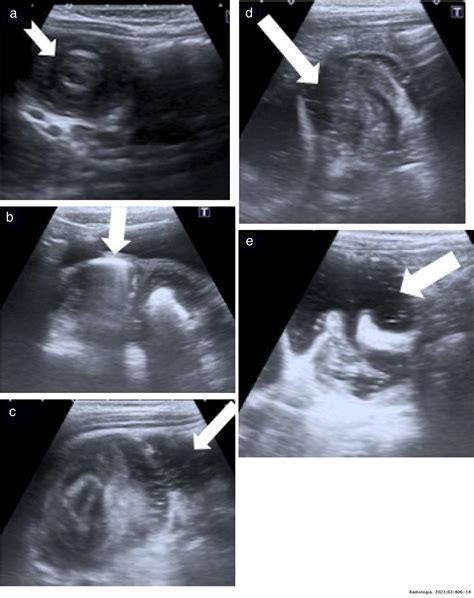

When performing an ultrasound to detect intussusception on ultrasound, radiologists look for specific signs that indicate the presence of intussusception. These signs include:

• Target or doughnut sign: This appears as concentric rings of alternating hypoechoic and hyperechoic layers, representing the invaginated intestine.

• Pseudo-kidney sign: This sign is seen when the intussusceptum (the invaginated segment) appears as a hypoechoic mass with a hyperechoic rim, resembling a kidney.

• Crescent-in-doughnut sign: This sign is observed when there is a crescent-shaped hypoechoic area within the doughnut sign, indicating the presence of mesenteric fat.

Ultrasound imaging is a non-invasive and readily available diagnostic tool that plays a pivotal role in the detection of intussusception on ultrasound. It provides real-time images of the abdomen, allowing physicians to visualize the intestinal layers and identify the characteristic "target" or "doughnut" sign, which is indicative of intussusception.